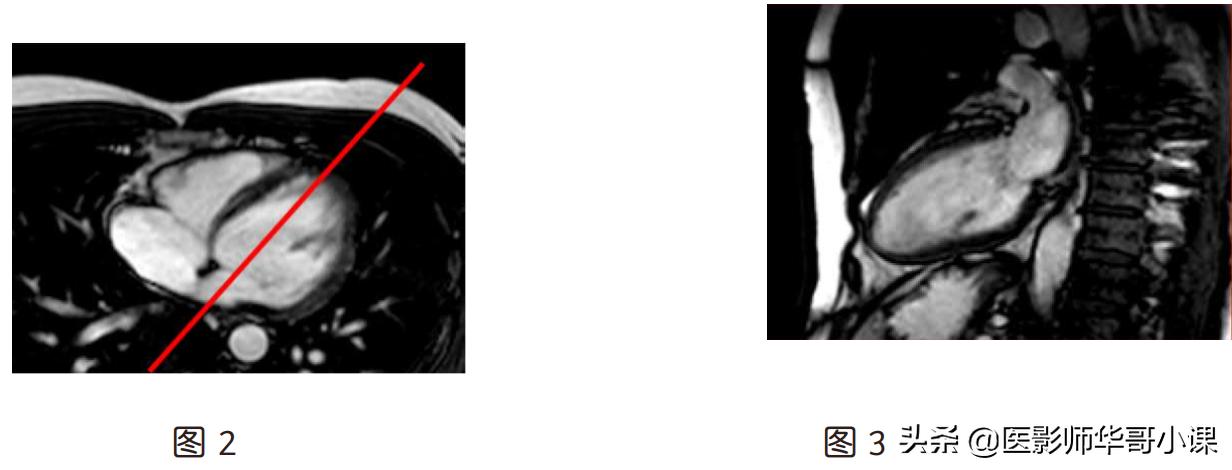

(1)假左两腔(图 3):在横轴位图(图 2)上,定位线平行室间隔

(2)短轴位(图 6):横轴位上(图 4)定位线垂直室间隔,假左两腔心(图 5)上定位像